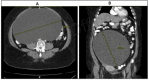

Mucinous cystadenomas are among the most common benign ovarian neoplasms. They are known for their massive size causing compressive effects ranging from pressure, pain, bloating, and urinary symptoms. Over time, these adnexal masses can lead to fatal complications, such as ovarian torsion or hemorrhage. Incidental findings of these tumors are common as many of these patients are asymptomatic. Pelvic examinations and imaging studies can be used to further diagnose symptomatic patients and aid physicians in developing an appropriate course of treatment. We report a rare case of a large mucinous cystadenoma, with a size of 25 × 25 cm and concurrent management of postmenopausal bleeding. We present the data from the admission of the patient to her discharge, including history and physical examination, diagnostic reports, transabdominal ultrasound, CT scan, surgical evaluation, and surgical-pathology reports. Abdominal pain can present in a variety of different scenarios, and ovarian masses only represent a small portion of the differentials. Mucinous cystadenomas constitute an even smaller percentage of these ovarian growths. As discussed in this case report, a large ovarian mucinous cystadenoma was compressing the surrounding structures resulting in a wide array of symptoms. The case describes the importance of extensive diagnostic evaluation and prompt surgical management of these ovarian tumors. It also brings attention to the significance of diagnosing a medical condition such as postmenopausal bleeding promptly to avoid potential negative outcomes.